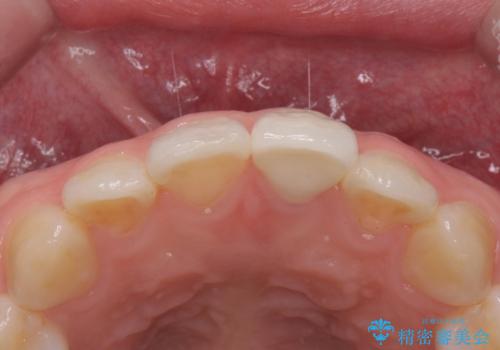

前歯の変色とガタつき ジルコニアクラウンでの修復

- 前歯の変色とガタつきが気になるとのことで来院された患者様です。

根管治療からやり直しを行った後、ジルコニアクラウンで修復することで、ガタつきと変色の両方を改善していきます。

ガタつきと変色の両方を改善することができ、大変喜んでいただけました。

少しのガタつきであれば、矯正治療を行わなくても改善できる場合があります。